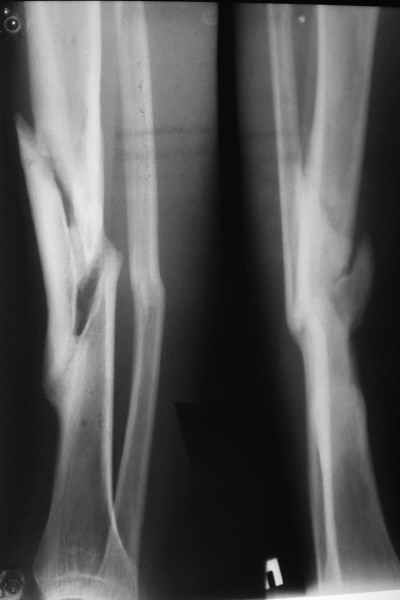

Неправильно сросшийся перелом голени

Уважаемые коллеги! На консультации больной предъявляет жалобы на хромоту (укорочение - 2см), боль в месте перелома при нагрузке (спортсмен).

Семь месяцев назад получил закрытый перелом, лечился консервативно в одной из больниц города. Как-бы кто лечил? Сам склоняюсь к LCP с костной пластикой.